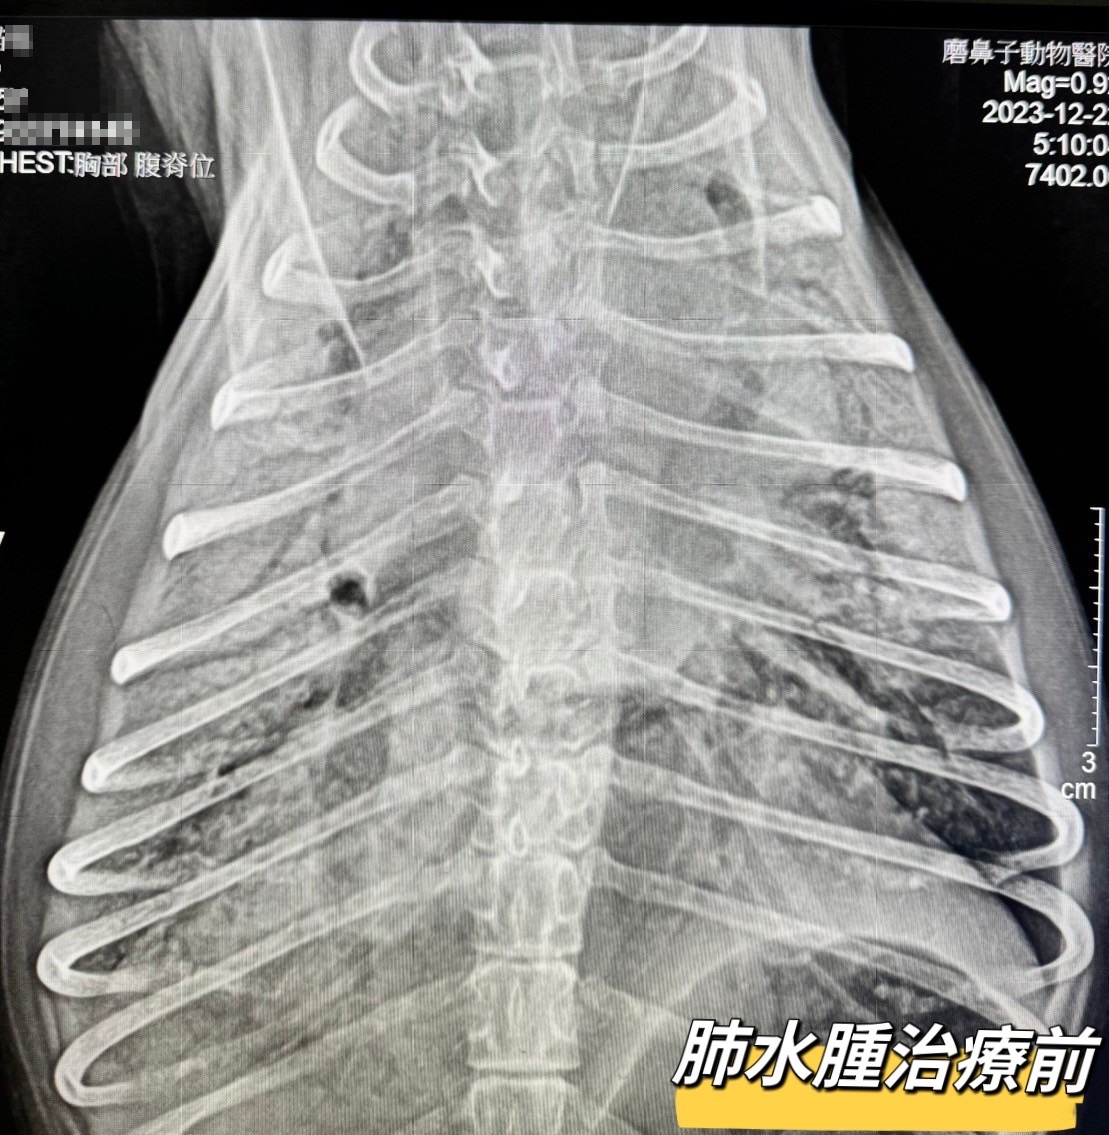

退行性二尖瓣疾病導致的肺水腫

Lucky最近出現咳嗽症狀,到了半夜更是沒辦法趴下休息心急的媽媽趕緊帶Lucky掛急診

經過

#胸腔X光 #心臟超音波 等檢查後

發現是退行性二尖瓣疾病(DMVD)導致「肺水腫」

趕快安排住進

#ICU氧氣病房

並進行相關治療

在醫療人員24小時不眠不休的照料下,毛孩很快就恢復穩定,順利脫氧出院囉

但日後也要開始按時服用心臟病藥物控制